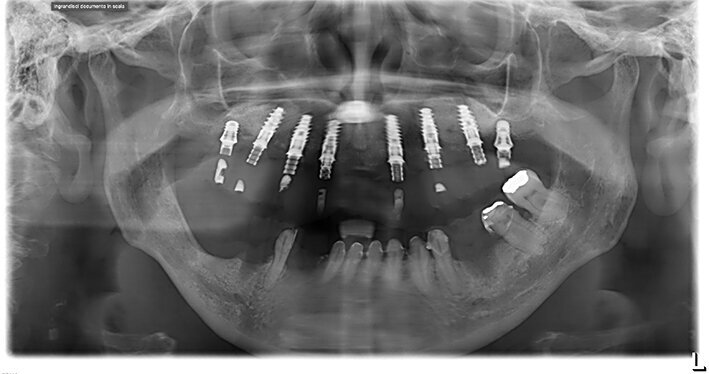

Inoltre da questa nuova ceratura dobbiamo ricavare una protesi radiografica con i punti di repere radiopachi che ci servirà per fare il matching con i nuovi file DICOM dell’osso rigenerato (Figg. 35, 36). Fatte le opportune verifiche nel software di chirurgia guidata, si pianifica l’intervento di posizionamento implantare (Figg. 37-40). Si programma lo stesso giorno della chirurgia anche il carico immediato degli impianti; decisione supportata dalla verifica istologica dell’osso rigenerato che dovrà comunque essere confermata il giorno del posizionamento implantare durante il quale si misurerà il torque di inserimento degli impianti e la stabilità primaria con il sistema OSSTELL mentor (Integration Diagnostics) che sfrutta l’analisi della frequenza di risonanza.

Procediamo quindi all’inserimento di sei impianti BLX Straumann (Straumann Group) (Fig. 43, 44), ed utilizziamo gli impianti posizionati nella tuberosità per stabilizzare la dima chirurgica e il provvisorio sul modello master di lavoro digitale. La funzionalizzazione del provvisorio immediato subito dopo l’intervento viene effettuata con l’utilizzo della tecnica DIL19 (Figg. 45, 46).